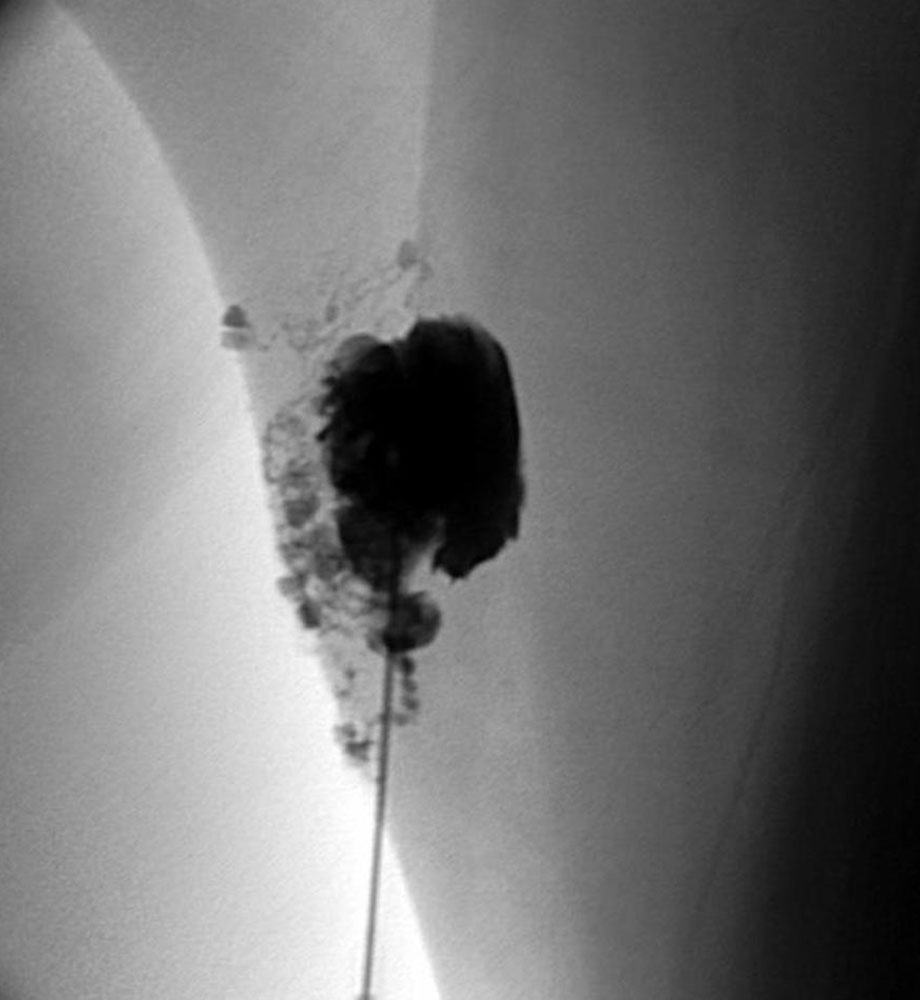

Above all, macrocystic lymphatic malformations can be cured or improved by sclerotherapy. A wide variety of sclerosing drugs are used for this purpose. OK-432 (picibanil) is a Japanese product consisting of fragments of a Streptococcus pyogenes which, when applied to a cyst, triggers an inflammatory immune response to the foreign protein and causes the cyst to shrink. The antibiotic doxycycline and the cytotoxic drug bleomycin are also widely used. They are usually applied under intraoperative sonographic control. Alcohol-containing substances such as STS (sodium tetradecyl sulfate) or polidocanol are also commonly applied under sonographic and radiological control.

This is sometimes combined with the insertion of a pigtail catheter, which can relieve the tissue in the case of severe post-interventional secretion and provide an access for repeated sclerotherapy without re-puncture. This procedure is very beneficial when treating retropharyngeal cysts and securing the airway. Bleomycin (with or without reversible electroporation) is particularly suitable for microcystic areas, which are usually infiltrated under sonography. Cutaneous or mucosal vesicles can be effectively treated by sclerotherapy but are prone to recurrence.